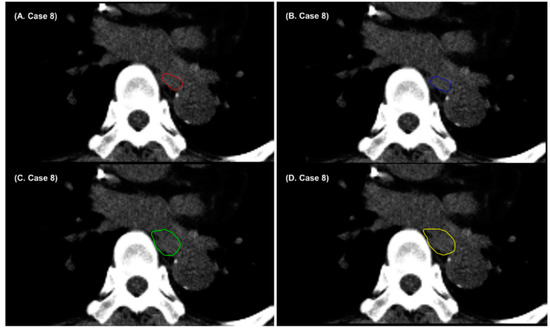

3. Results